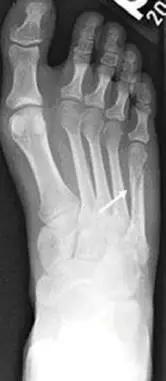

14.第五跖骨骨折

第五跖骨基底部骨折的不同类型:Stress 骨折;Jones 骨折:第五跖骨基底部以远 1 英寸内的骨折称为 Jones 骨折; Avulsion 骨折。

(来源:Radiopaedia)

Stress 骨折(来源:OrthoInfo-AAOS)

Jones 骨折正位片(来源:Radiopaedia)

Jones 骨折斜位片(来源:Radiopaedia)

第五跖骨骨折还有 dancer’s fracture。

dancer’s fracture 正位片(来源:footEducation)

dancer’s fracture 侧位片(来源:footEducation)